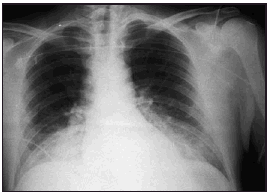

Figura 1. Radiografía del paciente del caso clínico en la que se muestra un infiltrado alveointersticial bilateral, compatible con edema pulmonar.

Pasadas 4 h el paciente presentó una disminución de la SaO2 al 91% con la misma FiO2. La auscultación pulmonar fue normal, con murmullo vesicular conservado bilateralmente. Se realizó una radiografía de tórax que demostró un infiltrado alveolointersticial bilateral no presente en la radiografía preoperatoria. Una gasometría arterial demostró: pH 7,28, PaCO2 40 mmHg, PaO2 73 mmHg, HCO3 18 mEd/l, SaO2 del 91%. Ante la sospecha de un edema agudo de pulmón secundario a EAVC se aumentó la concentración de oxígeno (FiO2 1) y se administró dosis de 250 mg de metilprednisolona.

El paciente evolucionó favorablemente, mejorando la SaO2, siendo posible disminuir la FiO2 a 0,4 y proceder a la extubación en las horas siguientes. Fue dado de alta a planta a las 24 h de su ingreso en UCI. En planta de neurocirugía se realizó una radiografía de tórax de control en la que el infiltrado había desaparecido.